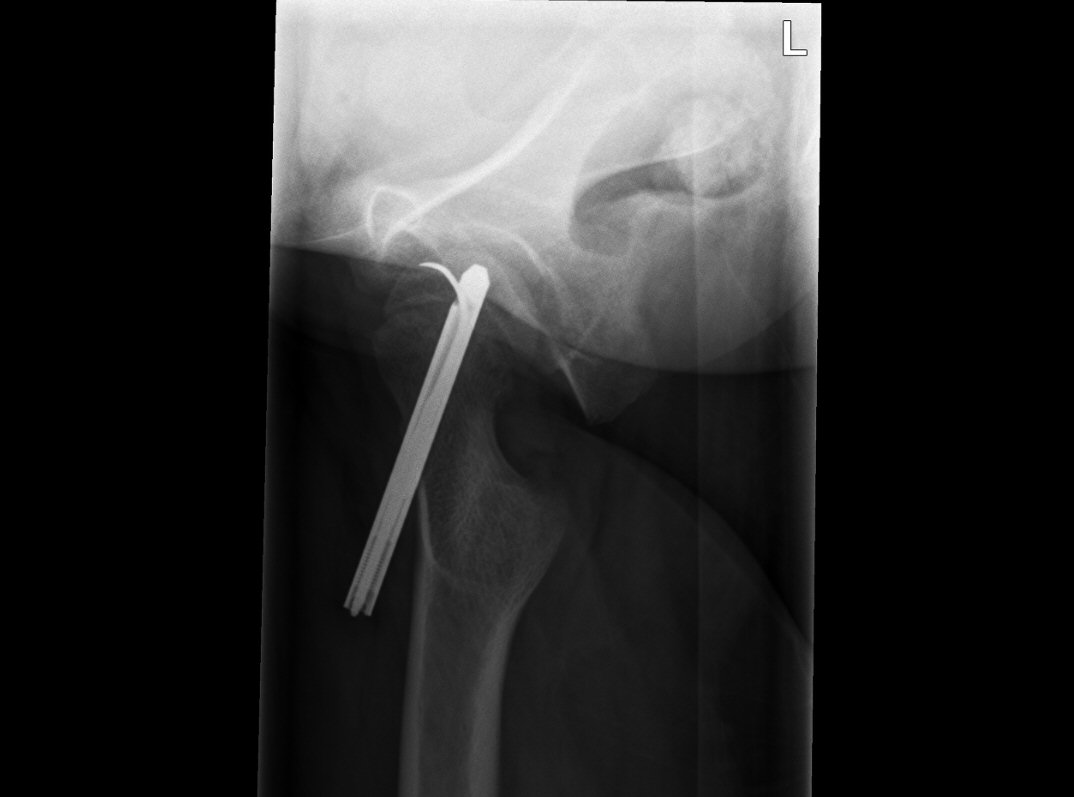

Fysiolys vänster höft akut, efter primär operation resp. innan spikextraktion efter 6 år

- Extraktion av spik/spikar efter att fysen slutits [3]